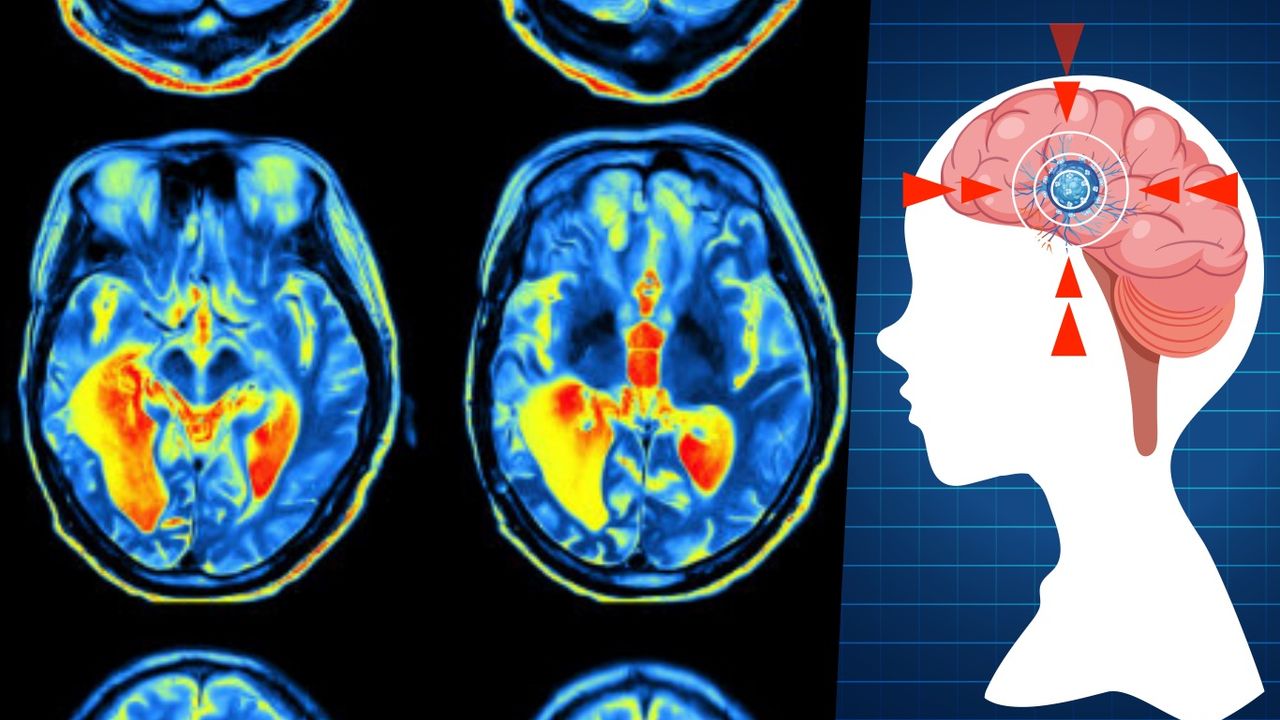

Araştırma, beynin yaşam boyu değişim gösterdiğini, ancak bu değişimin doğumdan ölüme uzanan sürekli ve pürüzsüz bir çizgi olmadığını ortaya koydu. Bunun yerine, beynin gelişimi ve organizasyonunun beş ayrı dönemde şekillendiği belirlendi:

Araştırmanın en çarpıcı bulgularından biri, beyin açısından ergenlik döneminin sandığımızdan çok daha uzun sürmesi. Beyin bağlantılarında verimliliğin arttığı tek dönem olan bu evre, 9 yaşında başlıyor ve 32 yaşına kadar devam ediyor. Bilim insanları bu dönemin aynı zamanda ruh sağlığı sorunlarının ortaya çıkma riskinin en yüksek olduğu zaman dilimi olduğunu vurguluyor.

Erken yaşlanma evresi 66 yaşında başlarken, beyinde keskin bir düşüş yerine organizasyon modeli değişiyor. Beyin, tek bir bütün olarak çalışmak yerine daha bölgesel gruplara ayrılarak faaliyet göstermeye başlıyor. Bu yaş aynı zamanda demans ve yüksek tansiyona bağlı beyin sağlığı sorunlarının görülmeye başladığı dönem.

83 yaşından itibaren beyin değişimleri hızlanıyor ve erken yaşlanma döneminde görülen bağlantı farklılıkları daha belirgin hâle geliyor. Bu yaş grubu için sağlıklı beyin verisi sınırlı olsa da eğilimlerin benzer olduğu belirtildi.